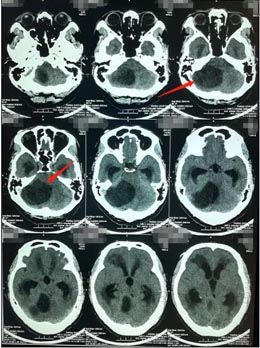

“门外一男一女吃力的扶着一个一米八的中年男子慢慢地跛行进来,我已经猜测到有八九分了:右侧小脑半球占位并梗阻性脑积水,小脑扁桃体下疝”,接诊的医院副院长、神经外五科的鲁明说。张先生的脑部影像检查也证实了鲁明的诊断:

由于肿瘤引起的继发性小脑扁桃体下疝,向下进入颈椎的椎管内,导致颈椎椎管狭窄,妨碍脑脊液循环形成脑积水。从治疗的角度,外科手术是必然的选择,目的是切除肿瘤后解除枕骨大孔和上颈椎对小脑、脑干脊髓、第四脑室及该区其他神经结构的压迫,在可能的范围内分离枕大池正中孔和上颈髓的蛛网膜粘连,解除神经症状,缓解脑积水。